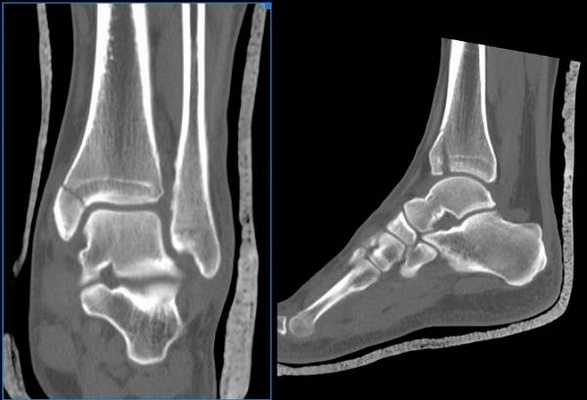

Компьютерная томография голеностопного сустава